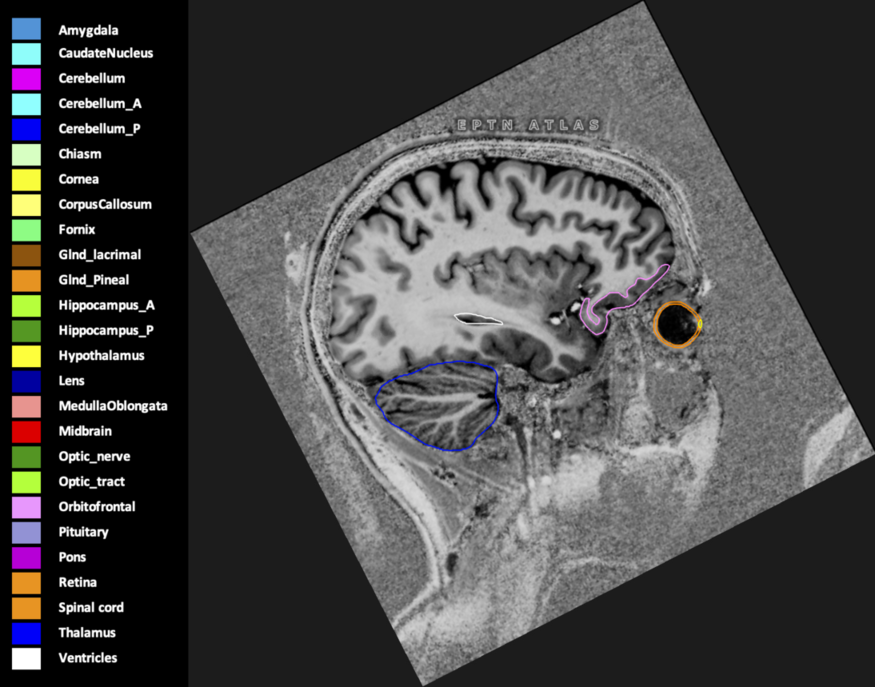

Included are all OARs known to be relevant for radiation-induced toxicity in neuro-oncology: brain, brainstem (midbrain, pons, medulla oblongata), chiasm, cerebellum (anterior & posterior), cochlea, cornea, hippocampus (anterior & posterior), hypothalamus, lens, lacrimal gland, optic nerve, pituitary, skin, and vestibular & semicircular canals. To further facilitate research on cognition, vision and radiological changes after irradiation of the brain, potential clinically-relevant OARs are included: amygdala, caudate nucleus, cerebellum (anterior & posterior), corpus callosum, fornix, macula, optic tract, orbitofrontal cortex, periventricular space (PVS), pineal gland, and thalamus.

Three-dimensional delineation of the 25 consensus OARs for neuro-oncology are shown on CT (WW/WL 120/40, 3000/600), 3T MR images, (T1Gd, T2FLAIR 1mm) and 7T MR (MP2RAGE 0.7 mm). All are presented in transversal, sagittal and coronal view.